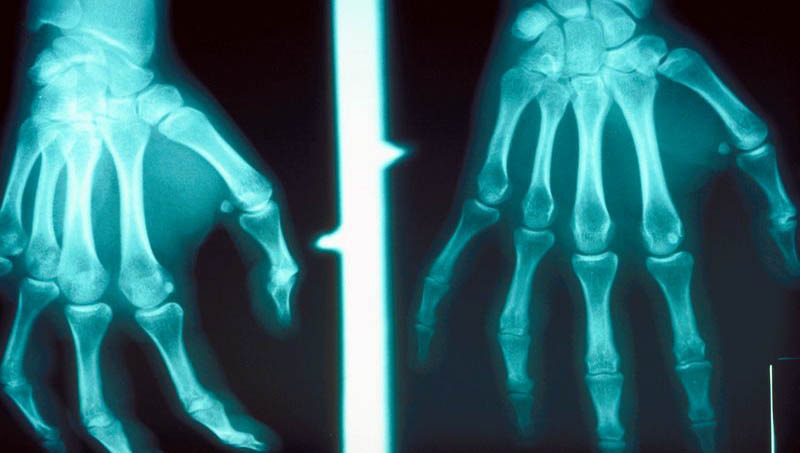

Biológiai terápia, spondarhtritisek, RA, PsA, immunológiai alapkutatás, onkológia és a biológiai terápia alkalmazása során felmerülő kérdések, radiosynovioorthesis, bizonyítékon alapuló fizioterápia, osteoporosis, képalkotó diagnosztika reumatológiai megbetegedésekben.